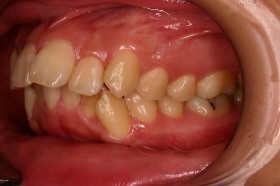

ご覧の症例は出っ歯を矯正治療でキレイにしたケースです。

このような場合では歯を抜いて矯正するか

、抜かずに矯正するか分かれるケースです。

ご覧の矯正歯科治療の場合は、抜いて矯正歯科

治療していますが東京世田谷矯正歯科センターでは

非抜歯矯正歯科治療をベースにしています。

どうしても抜かないとキレイにならない場合のみ

抜歯して矯正歯科治療しています。